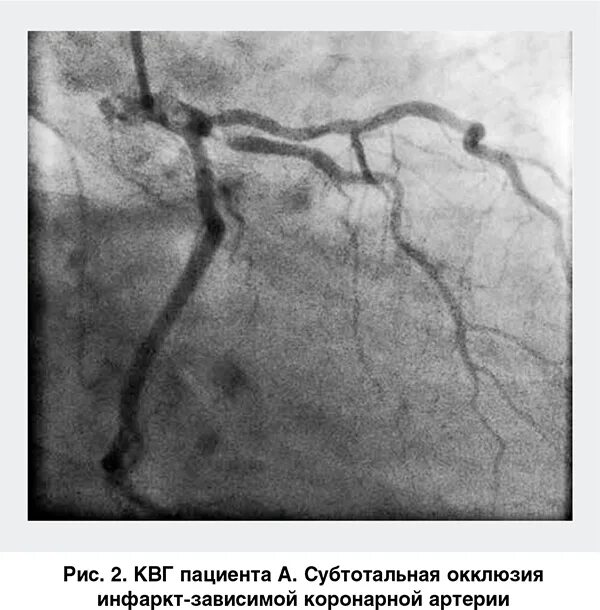

Атеросклероз коронарных артерий мкб 10